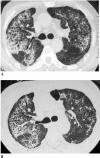

Results: Positive SARS-Co virus IgG antibody results were seen in 208 of 258 patients, with 21.3% (55 of 258 patients) still having a pulmonary diffusion abnormality (D(LCO) < 80% of predicted). By comparing the 155 survivors with positive SARS-CoV IgG antibody results and D(LCO) > or = 80% predicted with the 50 patients with negative SARS-CoV IgG results, we found that 53 patients with positive SARS-CoV IgG results and a lung diffusion abnormality had endured a much longer course of fever and received larger doses of glucocorticoid, as well as higher ratios of oxygen inhalation and noninvasive ventilation treatment. For these patients, 51 of 53 patients with positive SARS-CoV IgG results and a lung diffusion abnormality underwent pulmonary function testing after approximately 1 month. D(LCO) improved in 80.4% of patients (41 of 51 patients). Of the patients with a lung diffusion abnormality, 40 of 51 patients showed lung fibrotic changes in the lung image examination and 22 patients (55%) showed improvement in lung fibrotic changes 1 month later.

Conclusion: These findings suggest that lung fibrotic changes caused by SARS disease occurred mostly in severely sick patients and may be self-rehabilitated. D(LCO) scores might be more sensitive than HRCT when evaluating lung fibrotic changes.